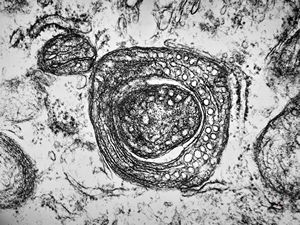

F,13y. | n.suralis … axonal neuropathy … Charcot-Marie-Tooth disease

Demyelinized nerve with bands of Büngner (square, inset) . P- perineurium, | E - epineurium. (Human, sural nerve.) Scale 0.2 mm.